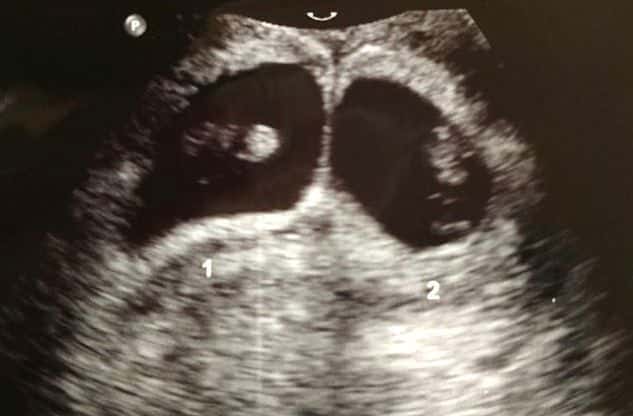

Early Twin Ultrasound at 7 Weeks

The earliest your doctor would likely order an ultrasound confirming twins would be 4 weeks pregnant. But unless you are going through fertility treatments, doing an ultrasound before 6 weeks isn’t very common, with the exception of complications. Women who are going through fertility treatments or have early complications may be able to have an early twin ultrasound at 4 or 5 weeks pregnant and find out they are pregnant with twins.

At four to five weeks after a pregnant woman’s last period the ultrasound commonly shows a small collection of fluid within the lining of the uterus that represents the early development of the gestational sac. At about five and a half weeks after a pregnant woman’s last period the ultrasound typically shows a gestational sac and within it we can see a 3-5 mm bubble-like structure, which is the yolk sac. At approximately six weeks after a pregnant woman’s last period, we can see a small fetal pole, one of the first stages of growth for an embryo, which develops alongside the yolk sac.

Yes! You’d need to have an ultrasound at 7 weeks to confirm a twin pregnancy. Your twin belly at 7 weeks may not look like much of a belly at all, so getting in to your doctor for an ultrasound is key to find out if you’re really having twins.